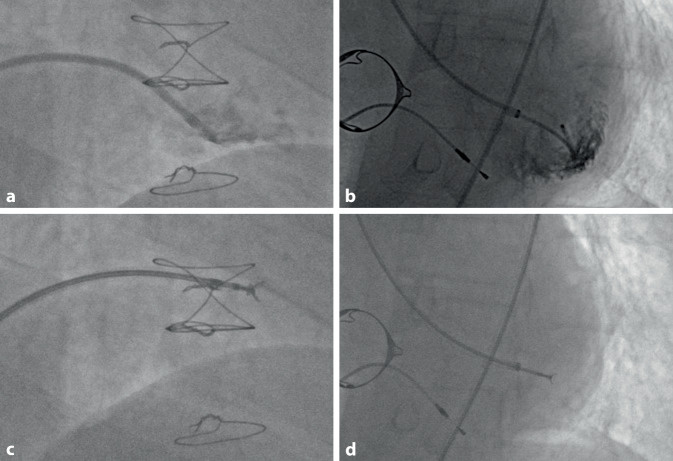

Üblicherweise wird der Zugang über die V. bzw. A. femoralis gewählt. Es kann aber auch der Zugang über die V. jugularis interna speziell bei transplantierten Patienten verwendet werden. Neuere Studien zeigen, dass für die linksventrikuläre Biopsie auch der Zugang über die A. radialis möglich ist. Die meisten heute erhältlichen Bioptome sind mit einer 7‑F-Schleuse kompatibel. Es empfiehlt sich, diese (70 cm) über einen 6‑F-Pigtail in den rechten oder linken Ventrikel vorzubringen. Die Biopsiezange sollte im geöffneten Zustand aus der Schleuse vorgeschoben und mit leichtem Druck auf das Myokard aufgesetzt werden. Ektopien und nicht anhaltende ventrikuläre Tachykardien sind sichere Zeichen für einen ausreichenden Kontakt des Bioptoms mit dem ventrikulären Myokard. Das Bioptom wird dann geschlossen und vorsichtig gezogen.

Für rechtsventrikuläre Biopsien sollte die favorisierte Entnahmestelle das interventrikuläre Septum (IVS) sein. Bei linksventrikulären Biopsien ist die laterale/posterolaterale Wand des Ventrikels retrograd über die Aortenklappe aufzusuchen. Zwei angiographische Beispiele für Myokardbiopsien sind in Abb. 12 dargestellt.

Risiken sind bei rechtsventrikulärer Biopsie insbesondere die Perforation (daher rechtsventrikulär möglichst septumnahe Biopsie) und bei linksventrikulärer Biopsie zusätzlich die zerebrale Embolisation. Für die Myokardbiopsie sollte die INR <2,0 sein. Insgesamt ist die akute Komplikationsrate (Perikarderguss, Schädigungen der AV-Klappen) mit <1 % sowohl für rechts- als auch linksventrikuläre Biopsien eher gering einzustufen [49, 50].